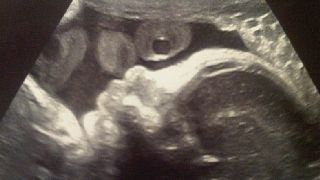

La gravidanza social di Shakira sembra piacere molto al popolo di Internet. E la bella cantante colombiana non perde occasione per postare foto e commentare in rete: "eccitante, dolcissimo"....

Gravidanza "social" per Shakira e Piqué